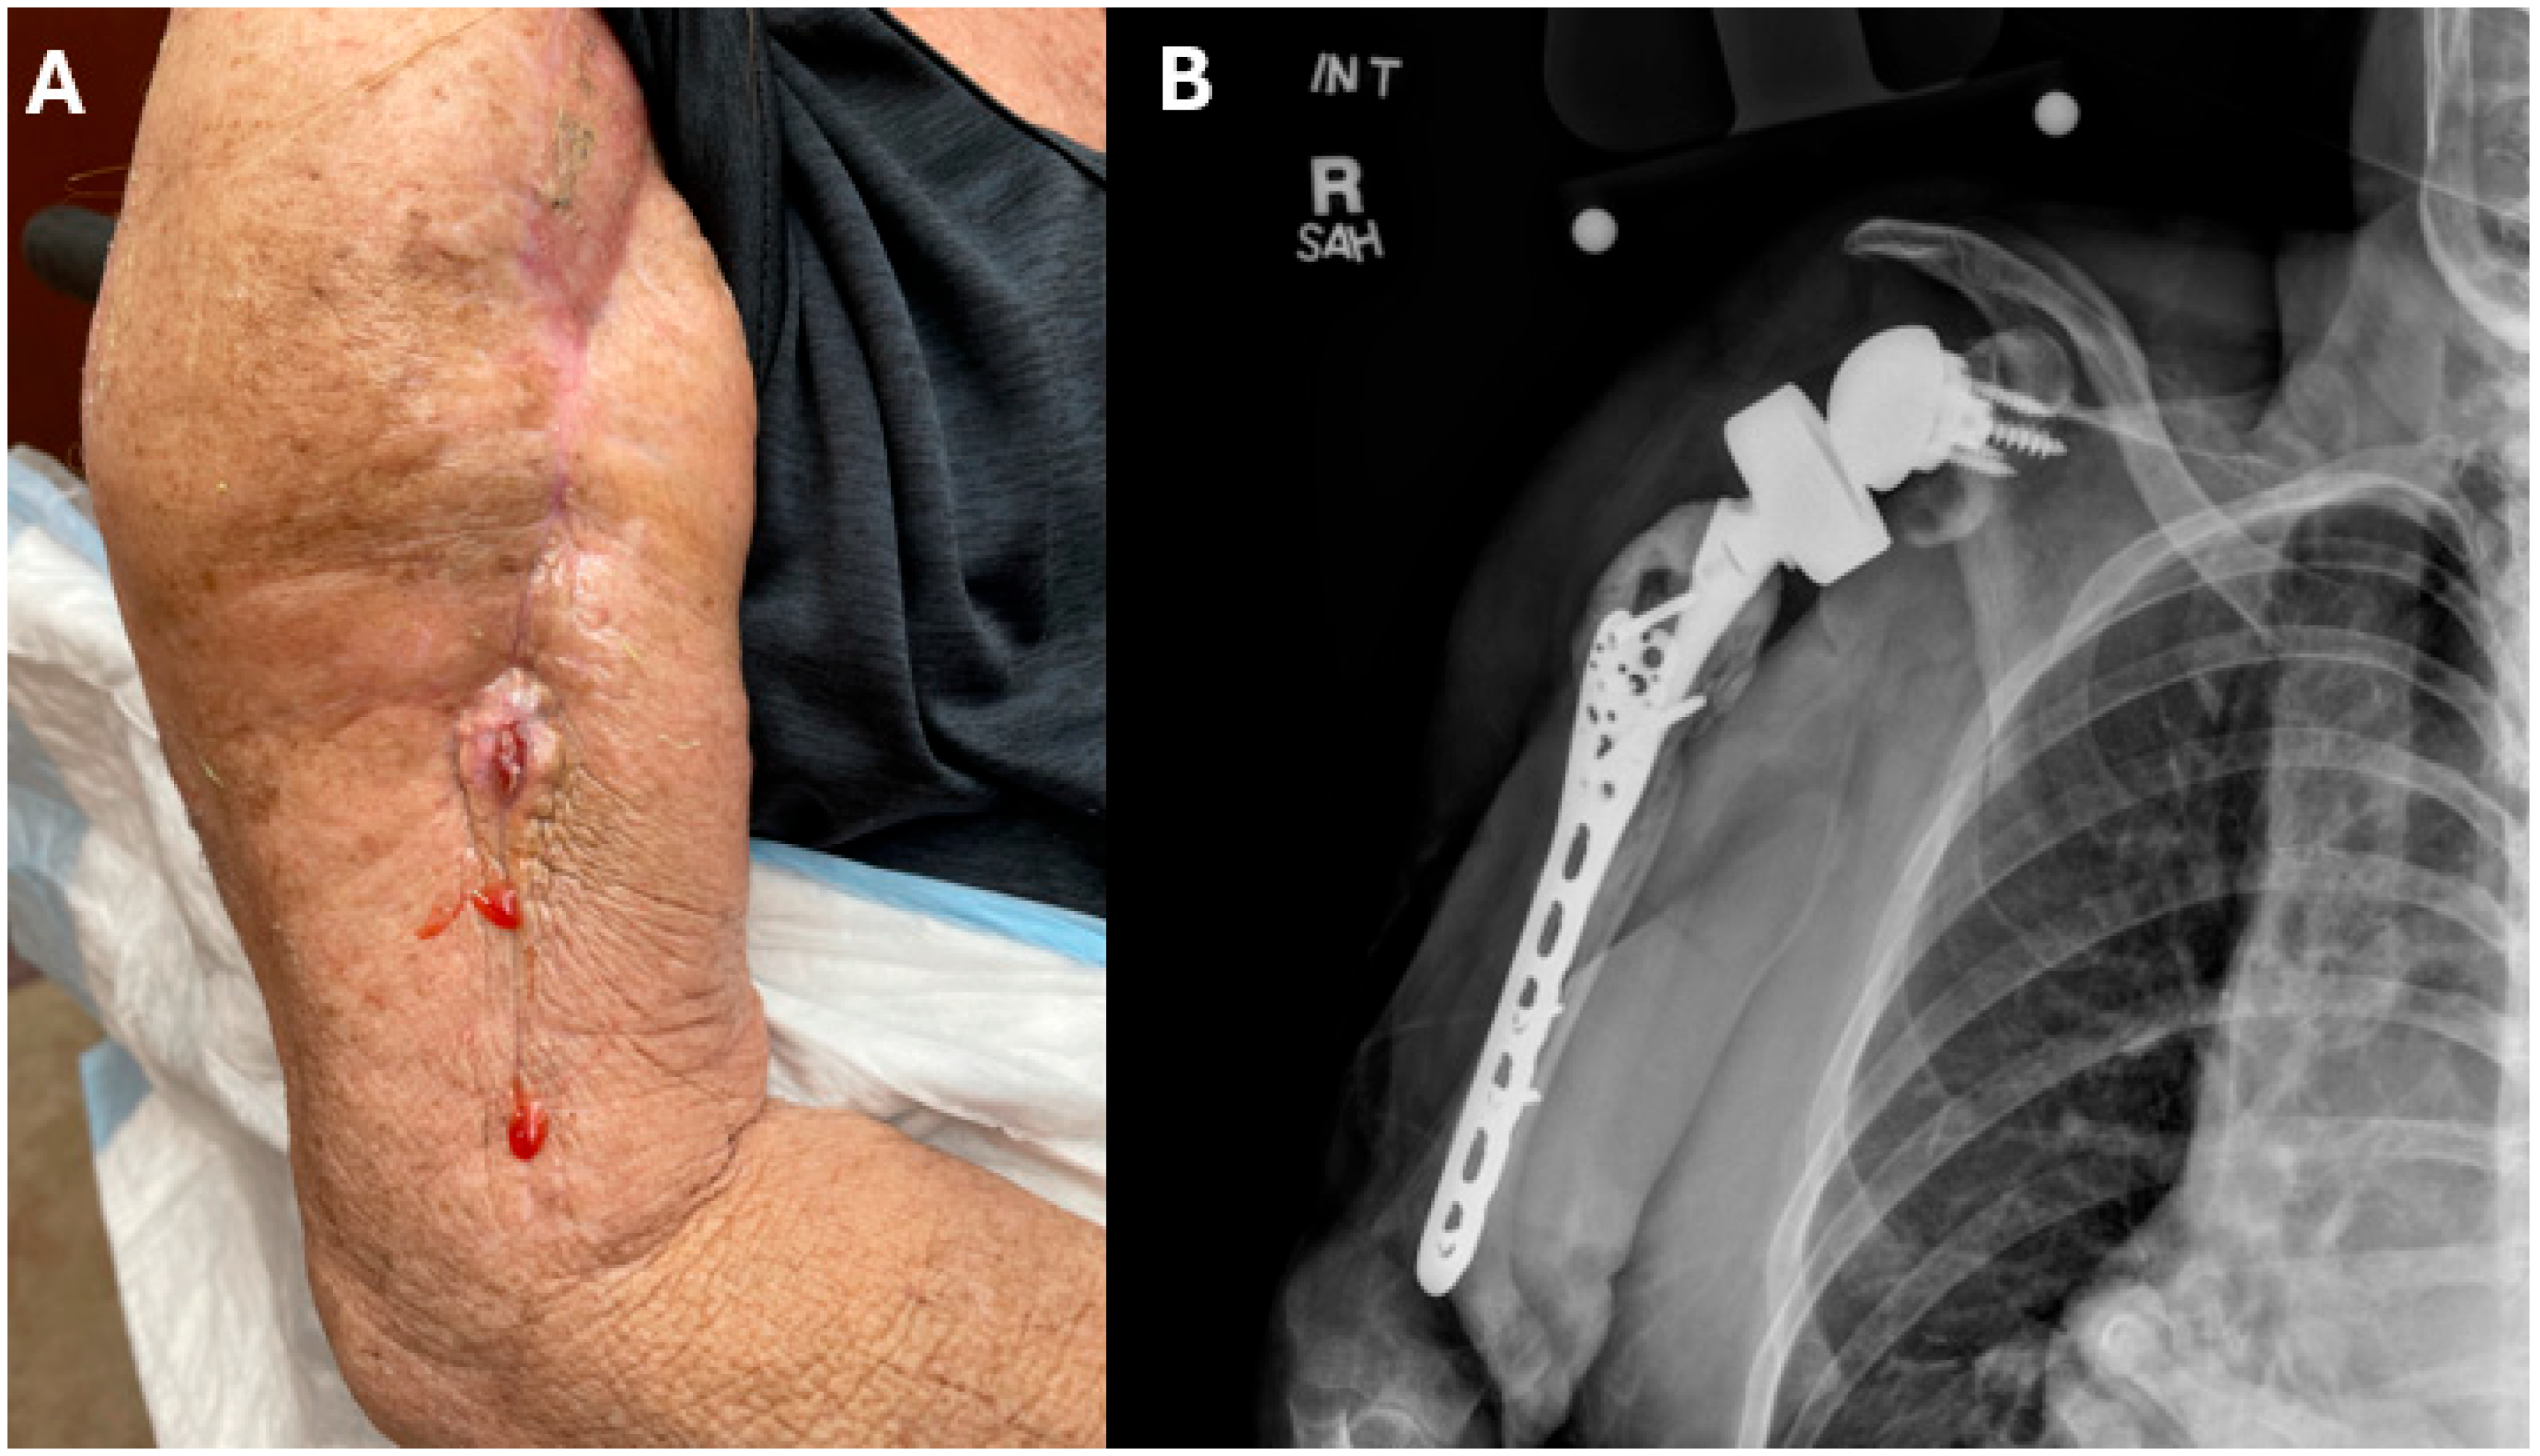

2. Case